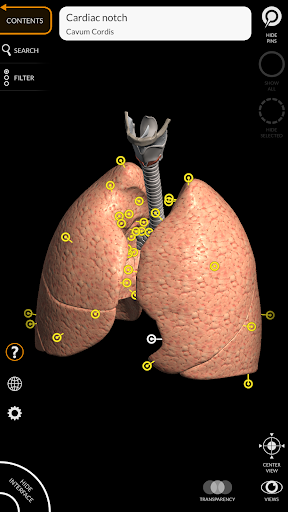

"Anatomy 3D Atlas" cho phép bạn nghiên cứu giải phẫu người theo cách dễ dàng và tương tác.

Thông qua giao diện đơn giản và trực quan, bạn có thể quan sát mọi cấu trúc giải phẫu từ mọi góc độ.

Các mô hình giải phẫu 3D đặc biệt chi tiết và có kết cấu lên đến độ phân giải 4k.

Việc phân chia theo vùng và chế độ xem được xác định trước giúp quan sát và nghiên cứu các bộ phận hoặc nhóm hệ thống riêng lẻ và mối quan hệ giữa các cơ quan khác nhau.

MÔ HÌNH GIẢI PHẪU 3D

• Hệ thống hô hấp